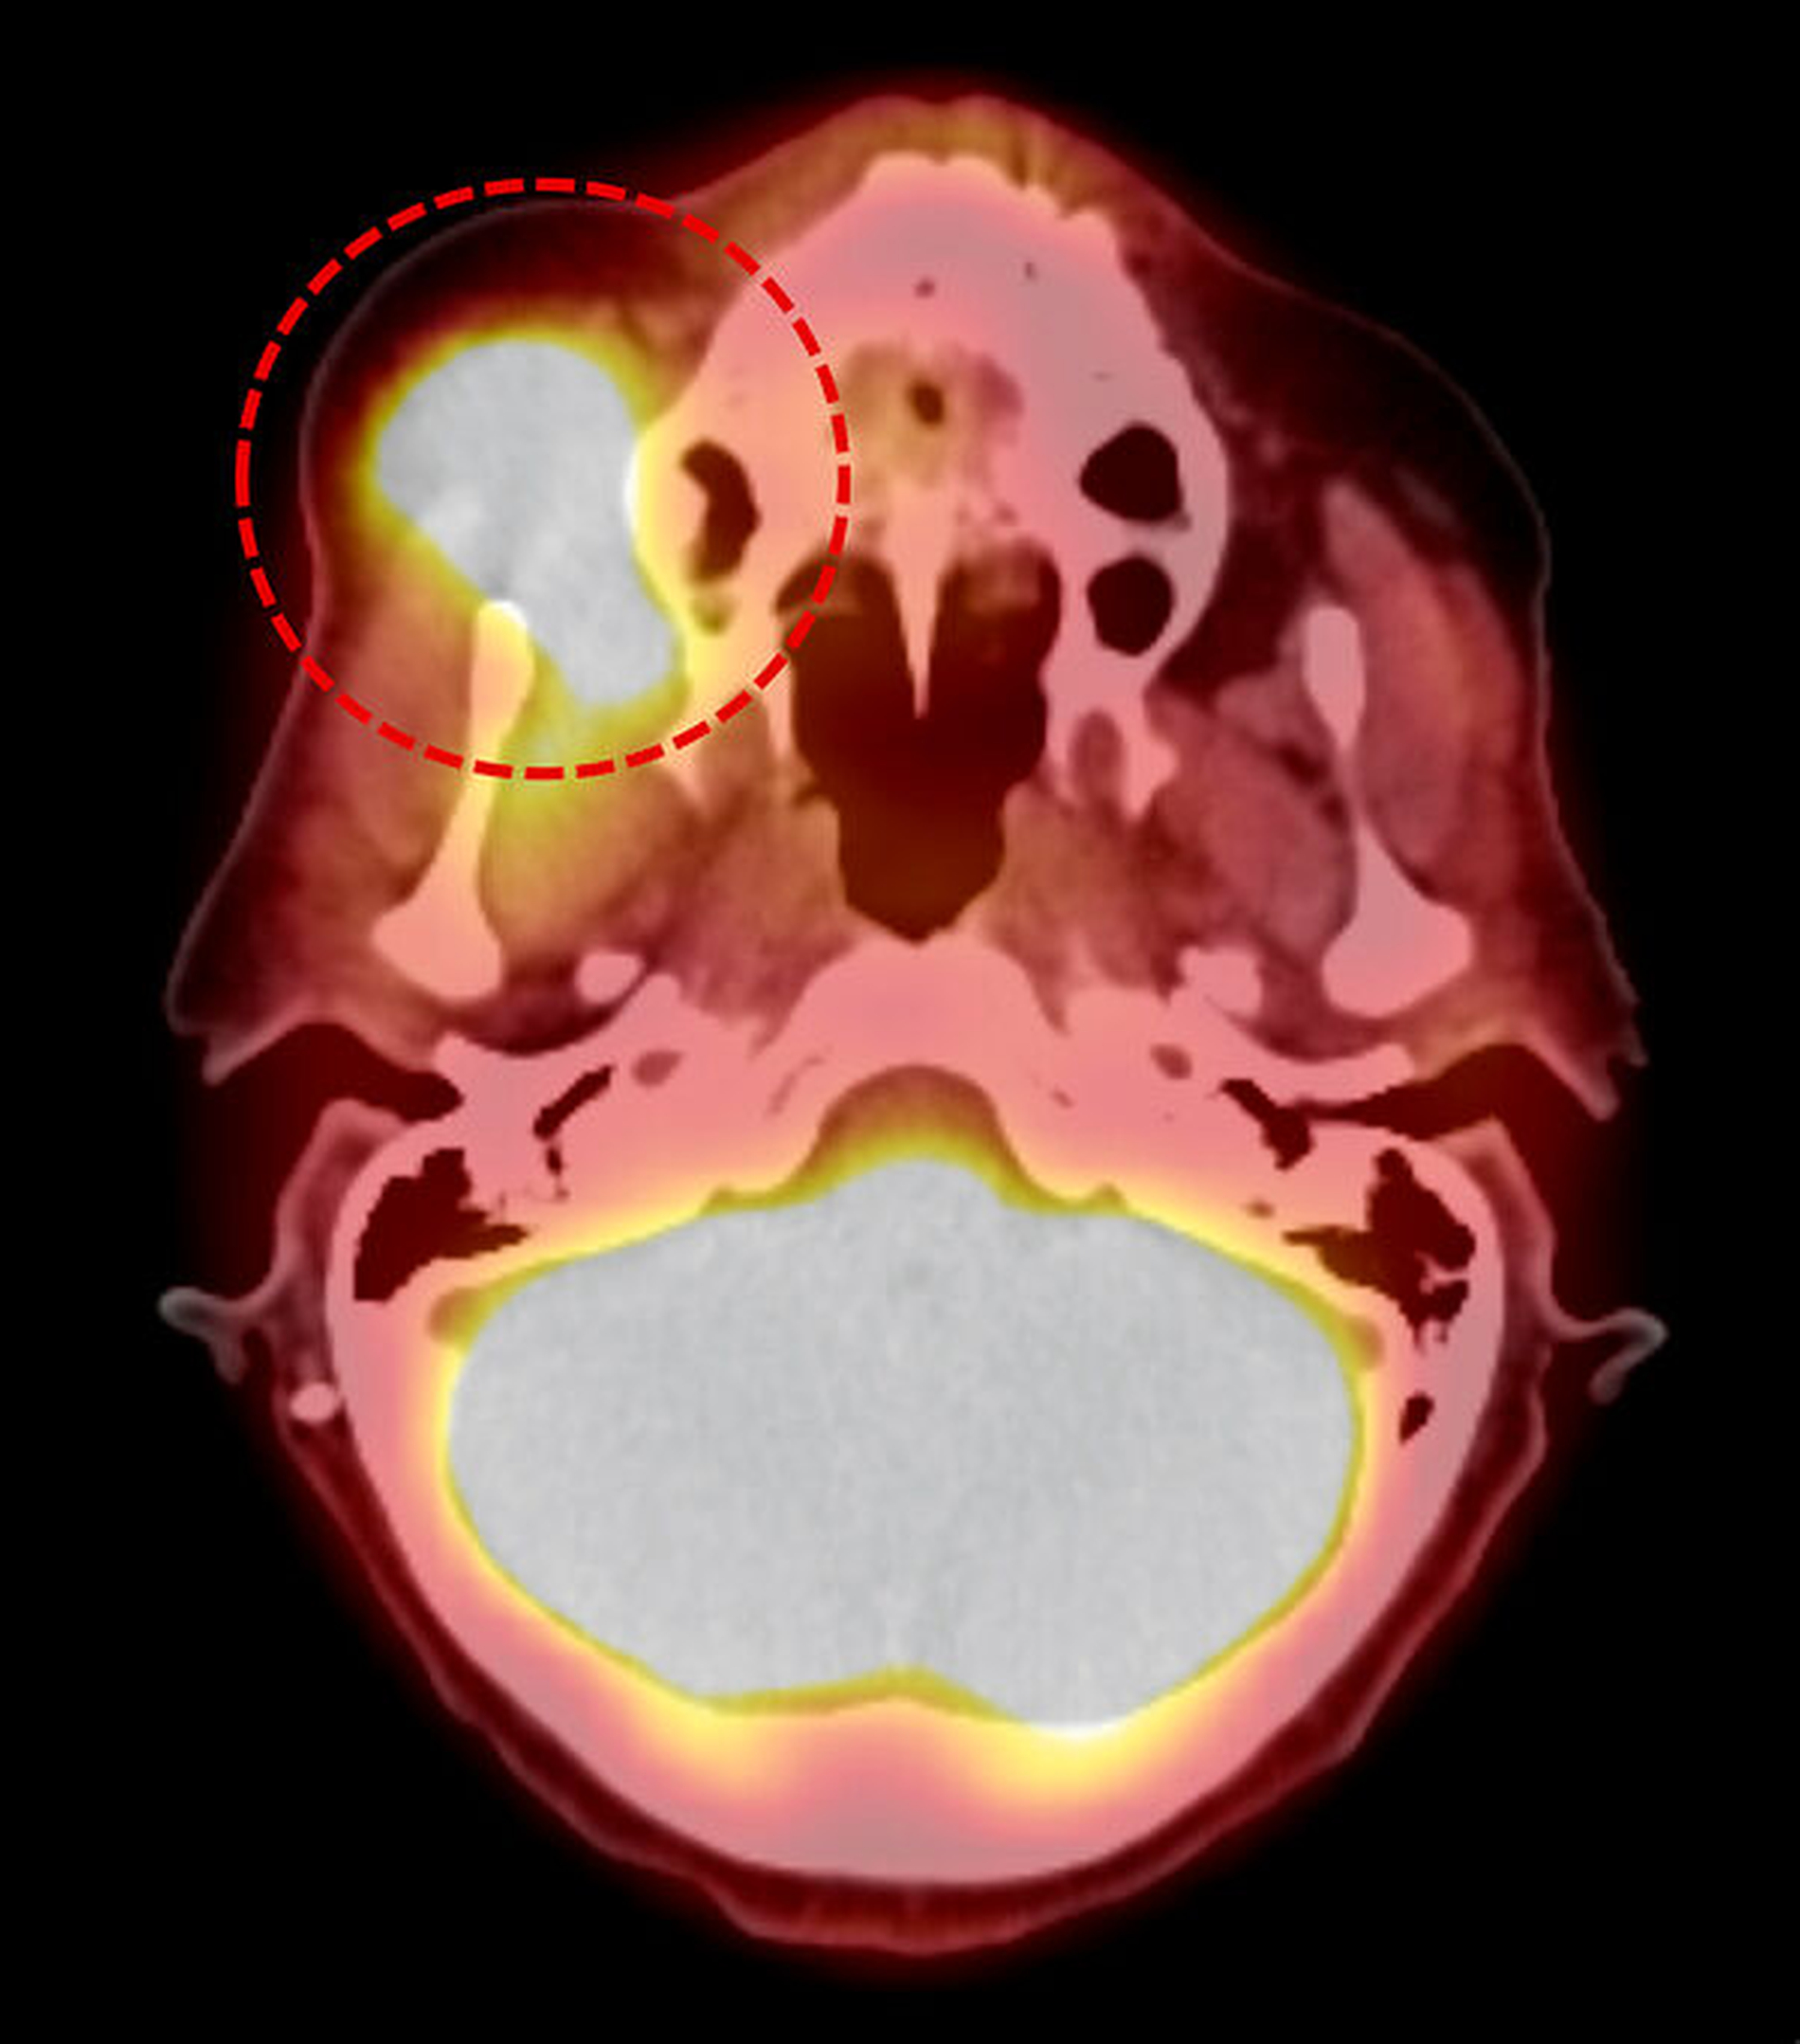

Es wurde die Diagnose eines hochmalignen, hochproliferativen Non-Hodgkin-Lymphoms (NHL) der B-Zellreihe, in erster Linie ein diffuses, großzelliges B-Zell-NHL (diffuse large B-cell lymphoma, DLBCL) gestellt. Speziell lag ein proliferationsaktives DLBCL, NOS (not otherwise specified) vom aktivierten B-Zell-Typ (activated B-cell type, ABC) mit einer MYC-Translokation vor (Abbildung 4). Das im Rahmen des komplettierenden Stagings durchgeführte FDG PET-CT zeigte einen intensiv verstärkten Glucosemetabolismus der vorbekannten Raumforderung in der rechten Wange (Abbildung 5). Insgesamt ergab sich kein Nachweis auffällig Glucosemetabolismus-gesteigerter Lymphknoten im gesamten Untersuchungsvolumen. Die knöchernen Strukturen zeigten keine suspekten osteoproliferativen oder osteodestruktiven Prozesse. Ausgehend von einem isolierten Befall der Weichteile rechts buccal wurde das NHL nach Abschluss des Stagings als Stadium I nach der Ann-Arbor-Klassifikation eingestuft.